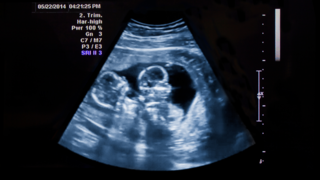

Why Babies Grow in Spurts Instead of a Straight Line Inside the WombOnce you get pregnant, your baby’s growth doesn’t always happen in a consistent manner. Rather, they grow in spurts, periods of rapid development followed by slower phases. This is a usual pattern and crucial for healthy development. Knowing why babies follow such a growth pattern during pregnancy can make you feel calmer during ultrasounds. It also helps you understand what to expect about your baby’s size and weight. It can also assist you in taking better care of yourself, both physically and emotionally.